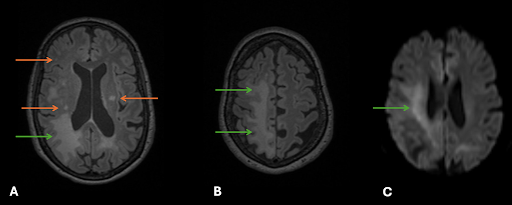

FLAIR Sequenz (A und B) zeigte sowohl ovaläre T2-hyperintense Läsionen vor allem im subkortikalen und periventrikulären Marklager (grüne Pfeiler), als auch ein flächiges T2-hyperintenses Territorium rechts parietookzipital. In der diffusionsgewichteten Sequenz (DWI, C) zeigt sich eine Diffusionsstörung des T2-hyperintensen Territoriums.

Durch die Bildgebung konnte ein Schlaganfall mit Gefäßverschluss ausgeschlossen werden. Die ovalären Läsionen sind typisch für Multiple Sklerose (MS). Das flächige T2-hyperintense Territorium hingegen ist charakteristisch für eine befürchtete Komplikation der Immuntherapie: die Progressive multifokale Leukoenzephalopathie (PML).